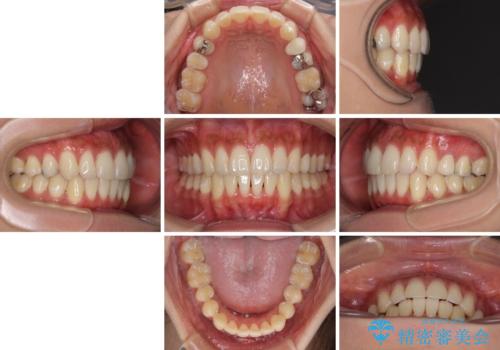

八重歯の再矯正 インビザラインでストレスなく矯正治療

- 学生の頃に矯正治療を行ったものの、保定を怠けてしまったことによる後戻りを気にして来院された患者様です。

根管治療が必要な歯があったため、矯正治療前に根管治療を行い、その後はインビザラインにより矯正治療を行うこととしました。

矯正治療後には根管治療を行った歯の補綴治療を行うこととしました。

下顎の八重歯が上顎歯列に収まる過程で咬みにくさがありましたが、最終的には、咬み合わせも安定し、きれいに歯列を整えることができました。